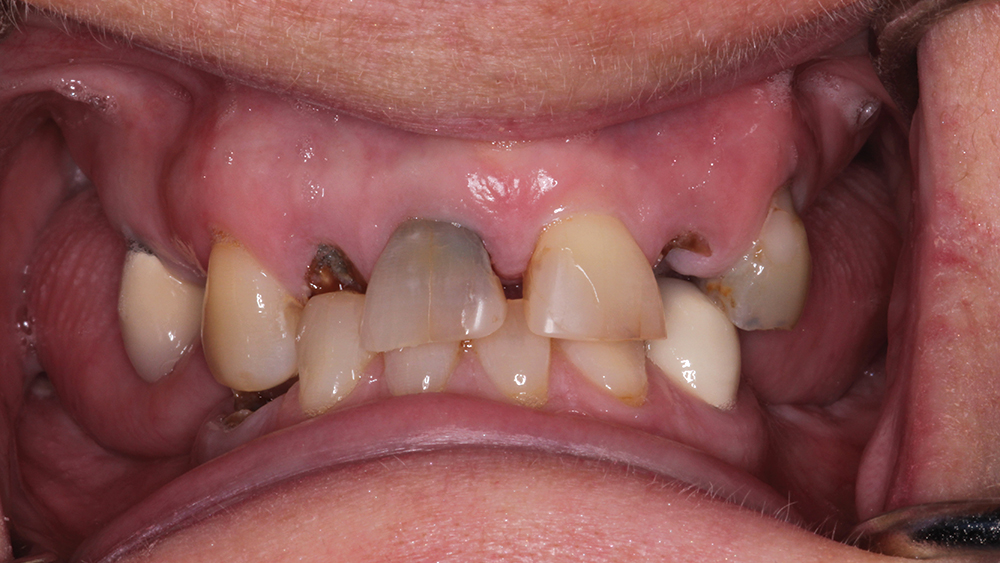

A patient sought treatment for advanced caries and periodontal disease in the maxillary arch, which had become painful and compromised her oral function. Although her remaining mandibular teeth also required replacement, she couldn’t afford to restore both arches at once and, like most patients, she placed a higher priority on her maxillary arch because of her esthetic needs. Following a discussion of treatment options, the patient requested a fixed restoration and was opposed to a removable appliance. At the surgical appointment, her maxillary teeth were extracted and Hahn™ Tapered Implants (Glidewell Direct; Irvine, Calif.) were placed. Sufficient primary stability was established for an immediate provisional appliance, which satisfied the patient’s request to leave the surgical appointment with a fixed restoration in place. After five months of healing and confirmation of the prosthetic design with a PMMA provisional, function, esthetics and quality of life were restored with a BruxZir Full-Arch Implant Prosthesis.